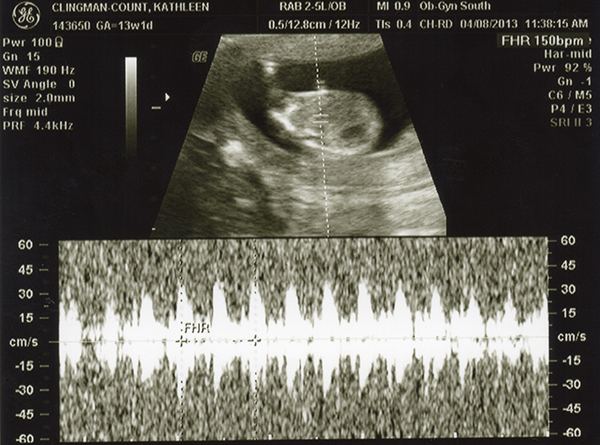

I had an ultrasound on Monday -- 13 weeks. I don't feel as though any of these are very clear pics. Even if they were better, I still wouldn't be any good with ultrasounds! Any of you experts able to make anything out with these? The tech guessed boy but the picture is not clear to me at all! She also kept saying the cord was between baby's legs and that we shouldn't go out and buy anything blue just yet. Any hope that it's a girl??